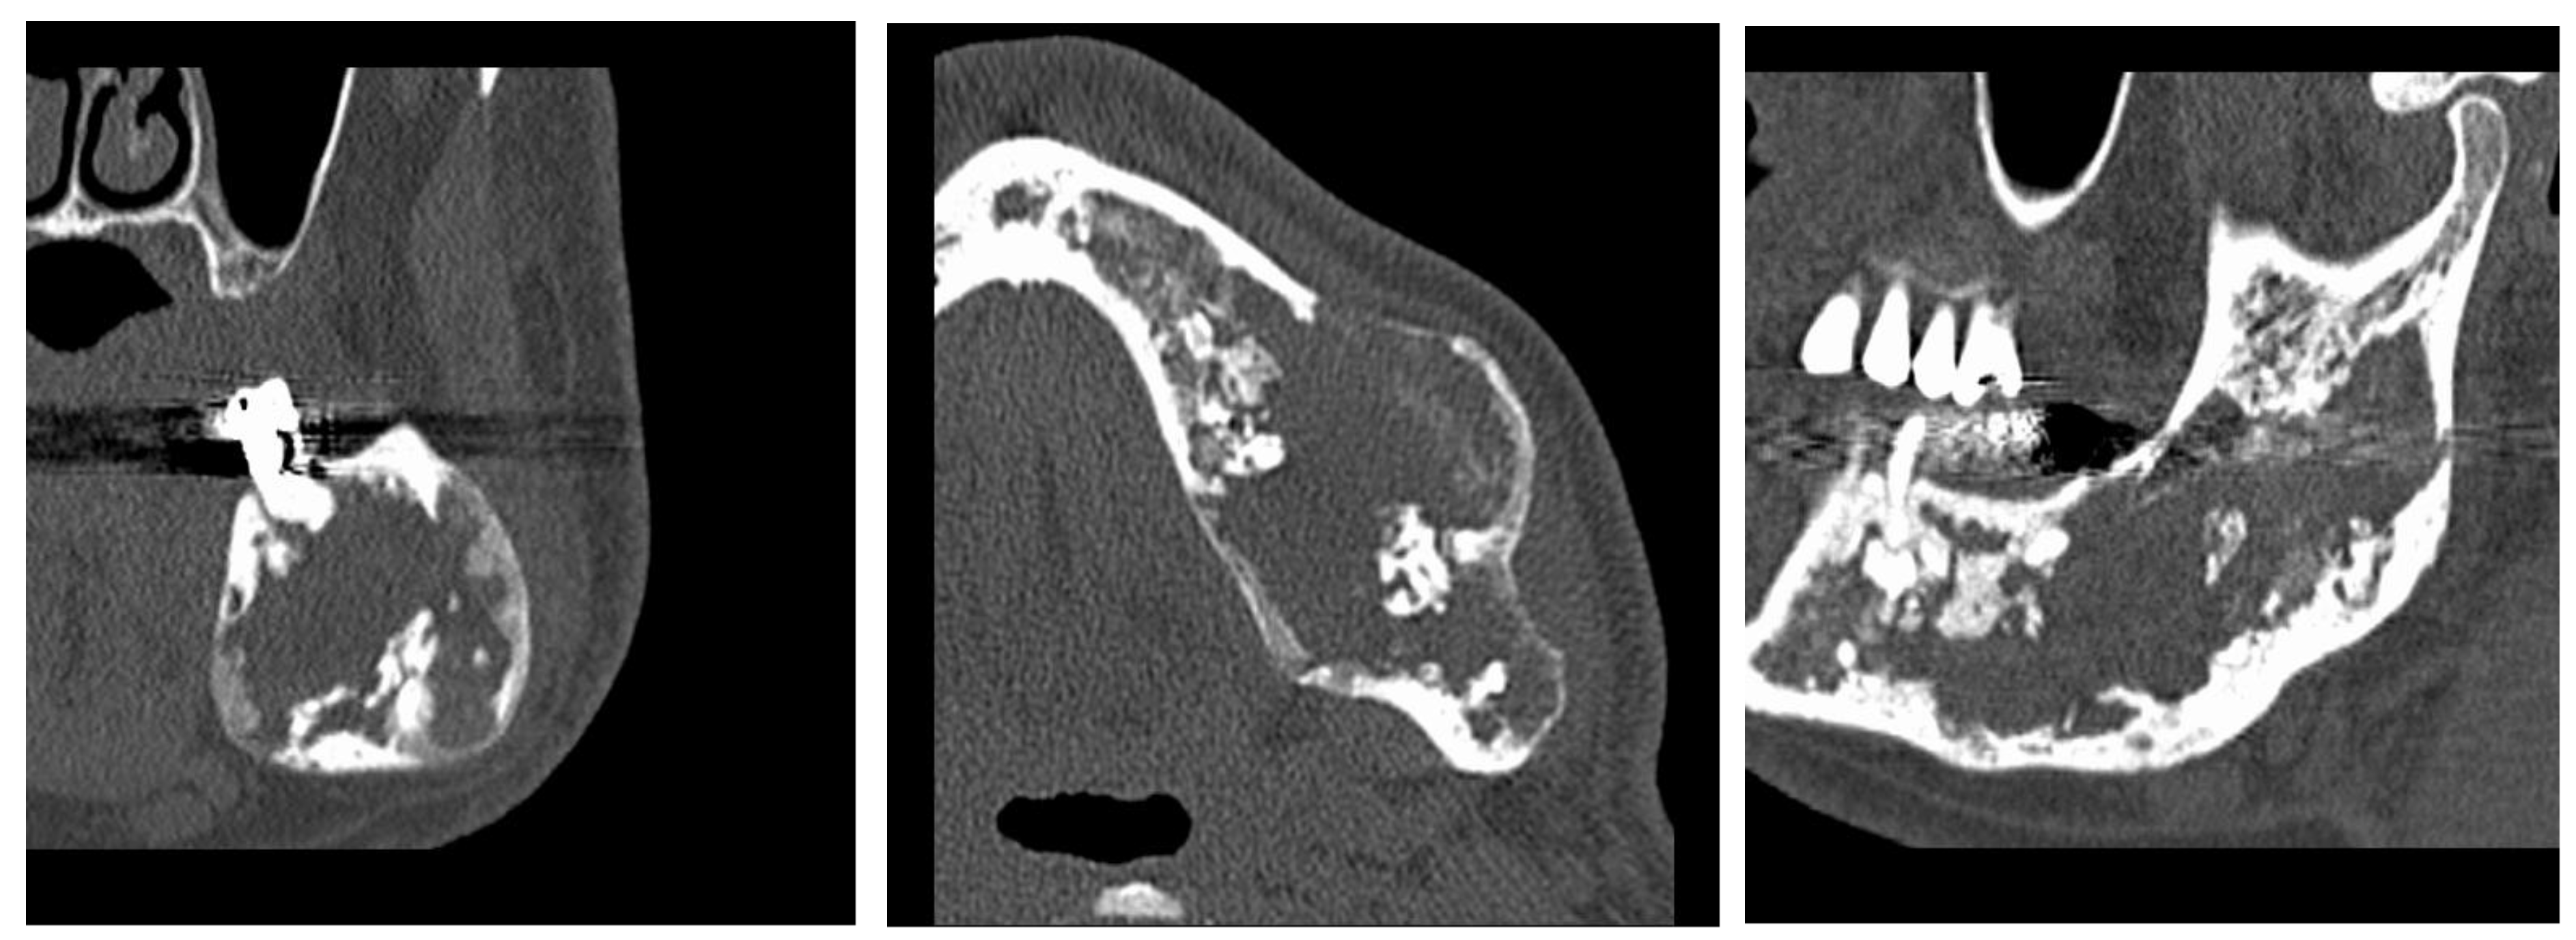

- phase 1: Conversion of the CT scan of the mandible from DICOM format to a 3D STL model